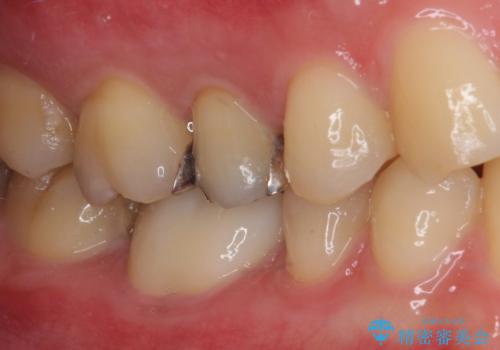

- 奥歯が欠けてしまったとのことで来院された患者様です。

おそらく歯が欠けて、装着されていた銀歯が外れてしまったと思われましたが、患者様はあまりはっきりとは覚えていないとのことでした。

咬合力が強いため、強化セラミッククラウンでの補綴治療を行うこととしました。